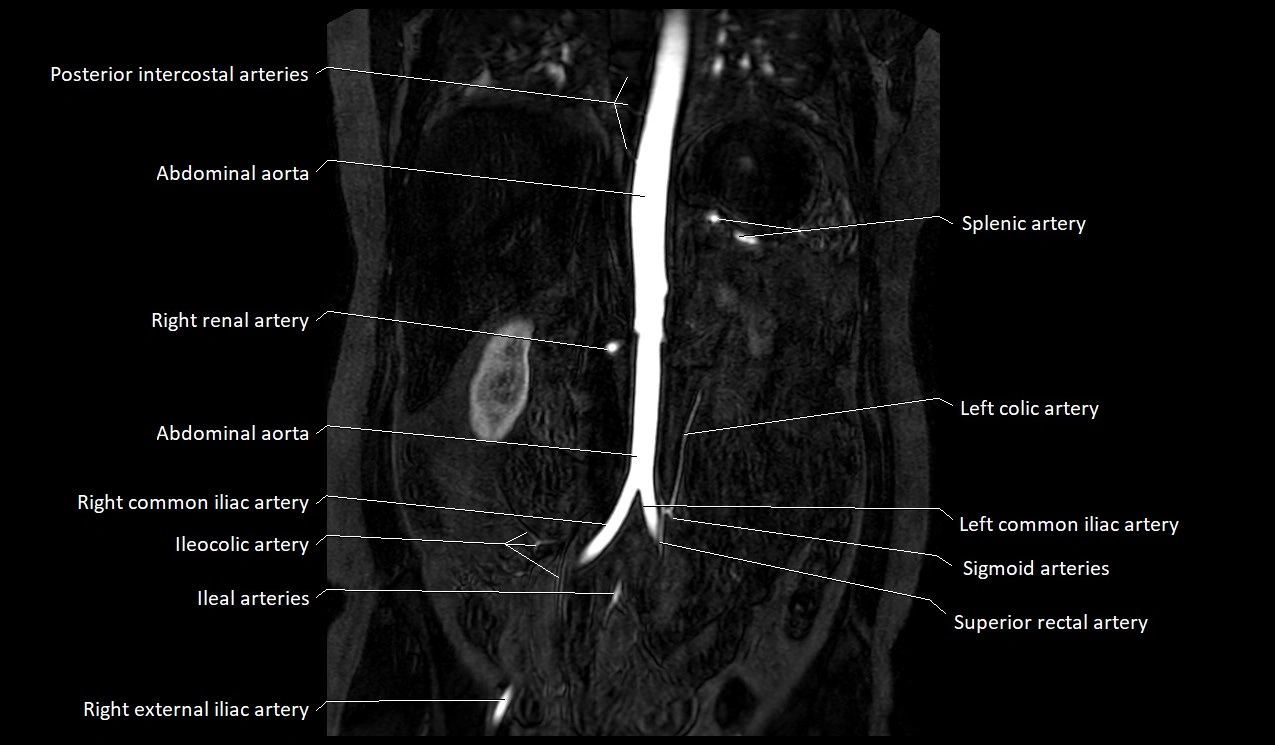

MRA Pelvis with Gadolinium:

-

Clearly delineates the origin, course, and anastomoses of the accessory obturator artery

Identifies connection with inferior epigastric artery, external iliac artery, or obturator artery

Excellent for detecting vascular variants prior to surgery

Useful in mapping pelvic vasculature in trauma, tumor embolization, or preoperative planning